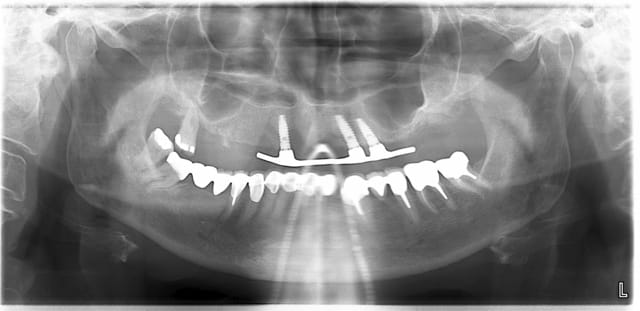

j'ai réalisé en juin 2008 ma seule pose d'implant chez une patiente sous biphosphonate. Cette patiente était sous BP depuis 4 ans; elle avait une très belle parodontite terminale avec abcès aigu qui a rendu l'extraction de sa 27 indispensable, et son médecin lui prescrivait ses BP sans lui avoir recommandé de faire une consult' chez son dentiste qu'elle n'avait pas revu depuis 10 ans.

comme elle ne ne disposait pas des moyens financiers nécessaires et que la cicatrisation s'était bien passée, je lui ai proposé un PDT avec 3 implants, barre d'ancrage, PAP et conservation d'une dent (en attendant le prochain implant);

L'AFSAPS considérant que la prise de BP par voie orale depuis plus de 3 ans ne contre-indique pas la pose d'implant,

la pose a été faite en flapless, la barre d'ancrage a été posée en 09/2008;

voici les photos avant de la pose de la barre en 09/2008 et la pano en 01/2009; RAS depuis